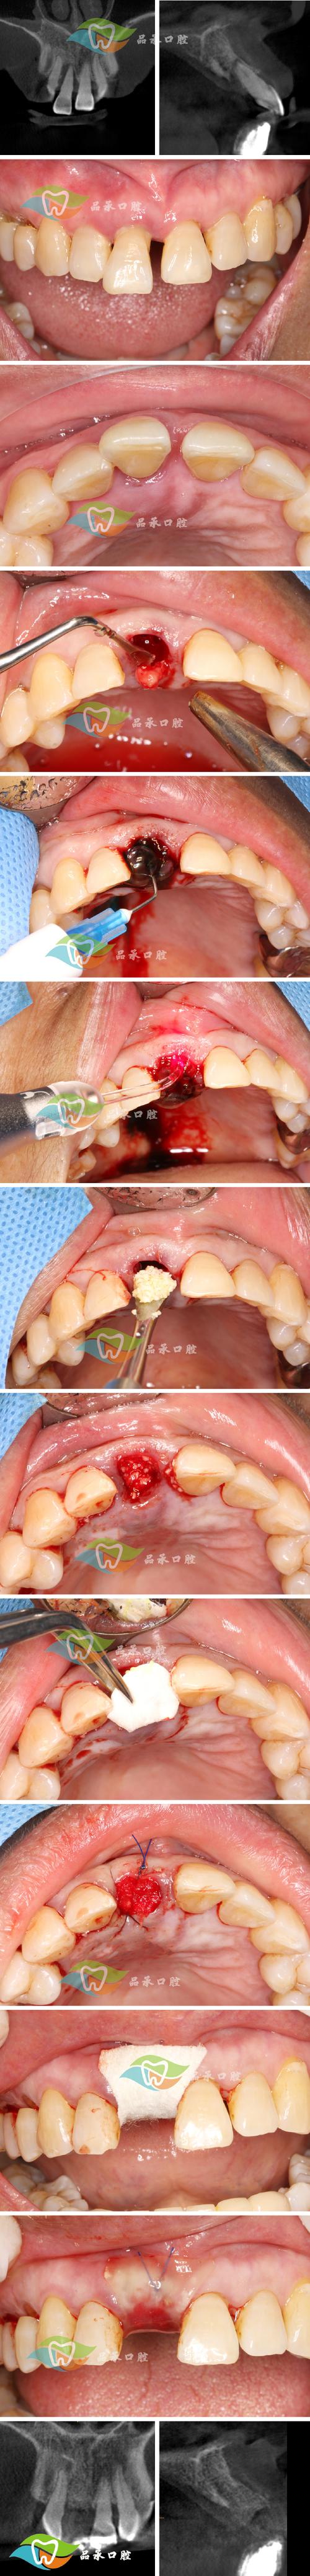

- 临床检查:评估口腔卫生状况、缺牙区软组织健康度,排除急性炎症(如牙周炎、根尖周炎)。

- 影像学评估:通过CBCT测量牙槽骨的高度、宽度、密度,判断骨缺损范围,设计植骨方案及种植体植入位置。

- 在缺牙区牙槽嵴顶做“梯形”或“弧形”切口,切开黏骨膜,翻瓣暴露骨缺损区域,彻底清除肉芽组织或炎性组织。

骨缺损处理与植骨

- 用球钻或超声骨刀修整骨缺损边缘,形成新鲜创面,促进骨细胞附着。

- 根据缺损大小选择合适植骨材料:若为颗粒状骨粉,可直接填入缺损区;若需支撑形态(如上颌窦提升),可配合使用骨胶原膜或钛网塑形。

屏障膜覆盖与缝合

- 将黏骨膜瓣复位,用可吸收缝线(如 Vicryl)严密缝合,关闭创口,避免植骨材料暴露。

- 复诊随访:严格按照医嘱复诊,通过CBCT观察骨愈合情况,通常植骨后3-6个月,骨密度和骨量达到稳定,可进行二期种植手术(安装种植体基台)。